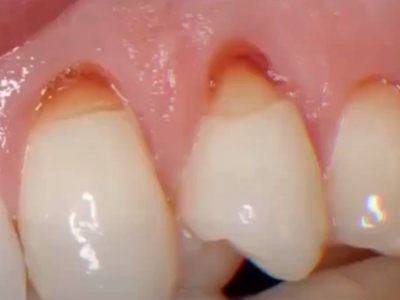

楔状缺损是一种非龋性牙颈部慢性损伤,是指发生在牙齿唇、颊面颈部的慢性硬组织缺损。典型缺损由两个夹面组成,口大底小,呈楔形。楔状缺损多发生于中老年人,主要原因是刷牙不当,防治措施是调整咬合关系,改善刷牙方法,配合相应的治疗。

楔状缺损与年龄相关,即年龄越大,缺损越重,患者多有横刷牙习惯,患牙为多颗甚至全口,常以口角附近的牙齿(尖牙、前磨牙)为重。典型表现为牙颈部缺损,呈楔形,由两个夹面组成,口大底小,缺损处质地坚硬,表面光滑,边缘整齐,无染色,轻微泛黄常为牙齿本色,严重时可导致牙髓腔暴露甚至牙齿横向折断,根据缺损深浅不同,可伴有牙齿敏感甚至疼痛。

不正确的刷牙方法,尤其是横刷法是发生楔状缺损的主要原因,因为牙颈部结构比较薄弱,易发生磨损。另外,颊面牙颈部是咬合应力集中区,长期的咀嚼压力使牙体组织疲劳,应力集中区出现破坏,也会造成楔状缺损。龈沟内酸性渗出物,也与楔状缺损的发生有关。